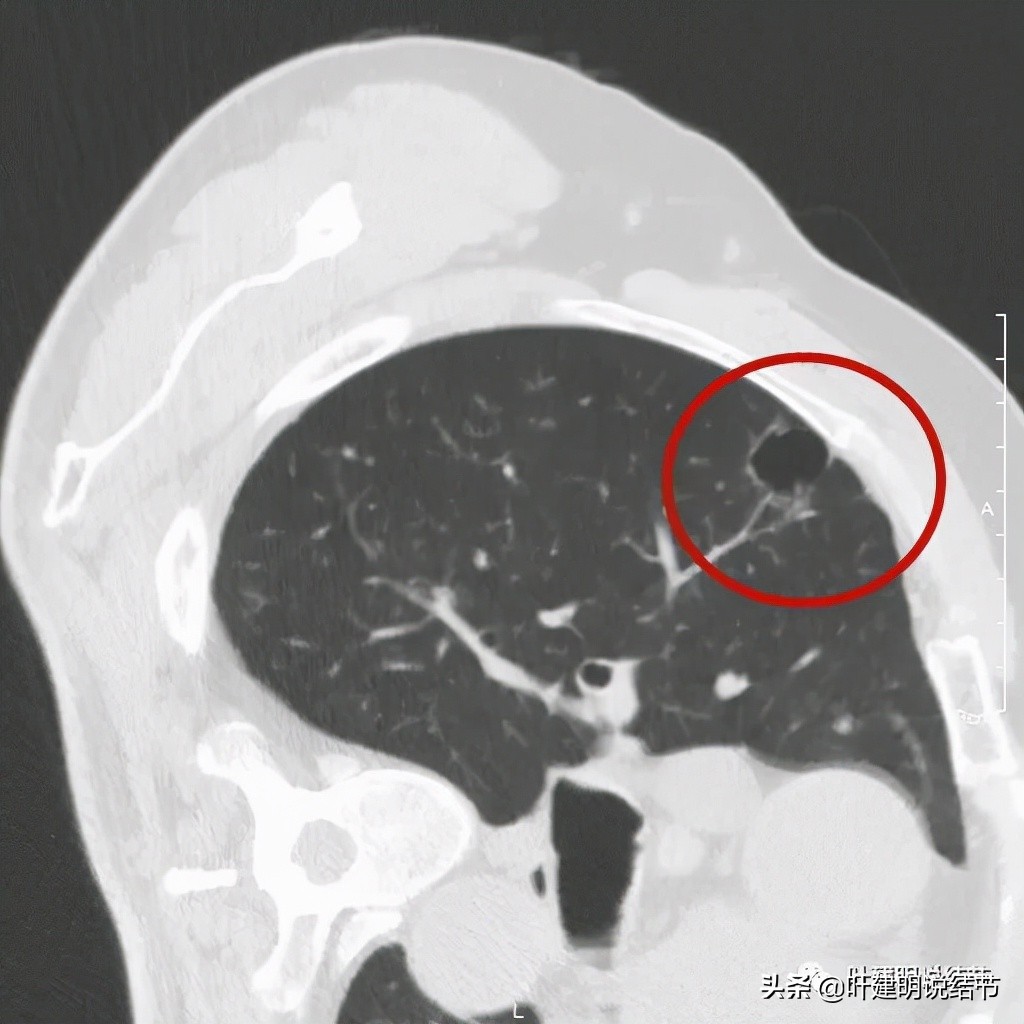

以上诸图是病灶4:考虑囊腔型肺癌可能性大,壁厚薄不均,内壁不光滑,有血管进入病灶,有少许密度偏高的成分,但纵隔窗上未见,不是真正意义上的实性成分。

感觉怎么囊壁实性成分密度有点显得高,粉色箭头所示处明显密度不均,偏高密度;蓝色箭头示有胸膜牵拉;砖色箭头示分叶征;桔色箭头示血管走向病灶。我觉得关键是病灶位置好,紧贴胸壁,能局部楔形切除,对肺功能影响小,又能去除危险。倾向切了它!